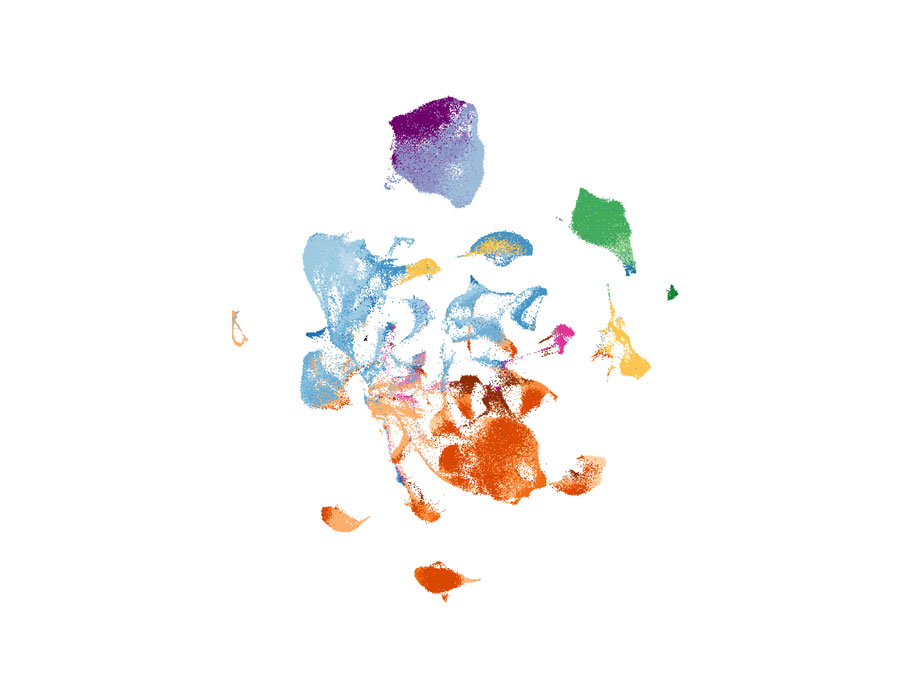

Studies of uterus transplant recipients reveal how immune cells shape pregnancy outcomes, an amino acid cocktail enhances nanoparticle delivery of therapeutic mRNAs in mice, and more this week in #ScienceTranslationalMedicine. scim.ag/3NgmFcX